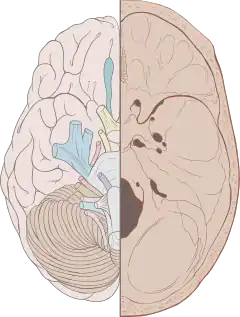

The foramina in the base of the skull are exit and entry points for veins, arteries and cranial nerves.

The cranial nerves as they exit through various foramina.